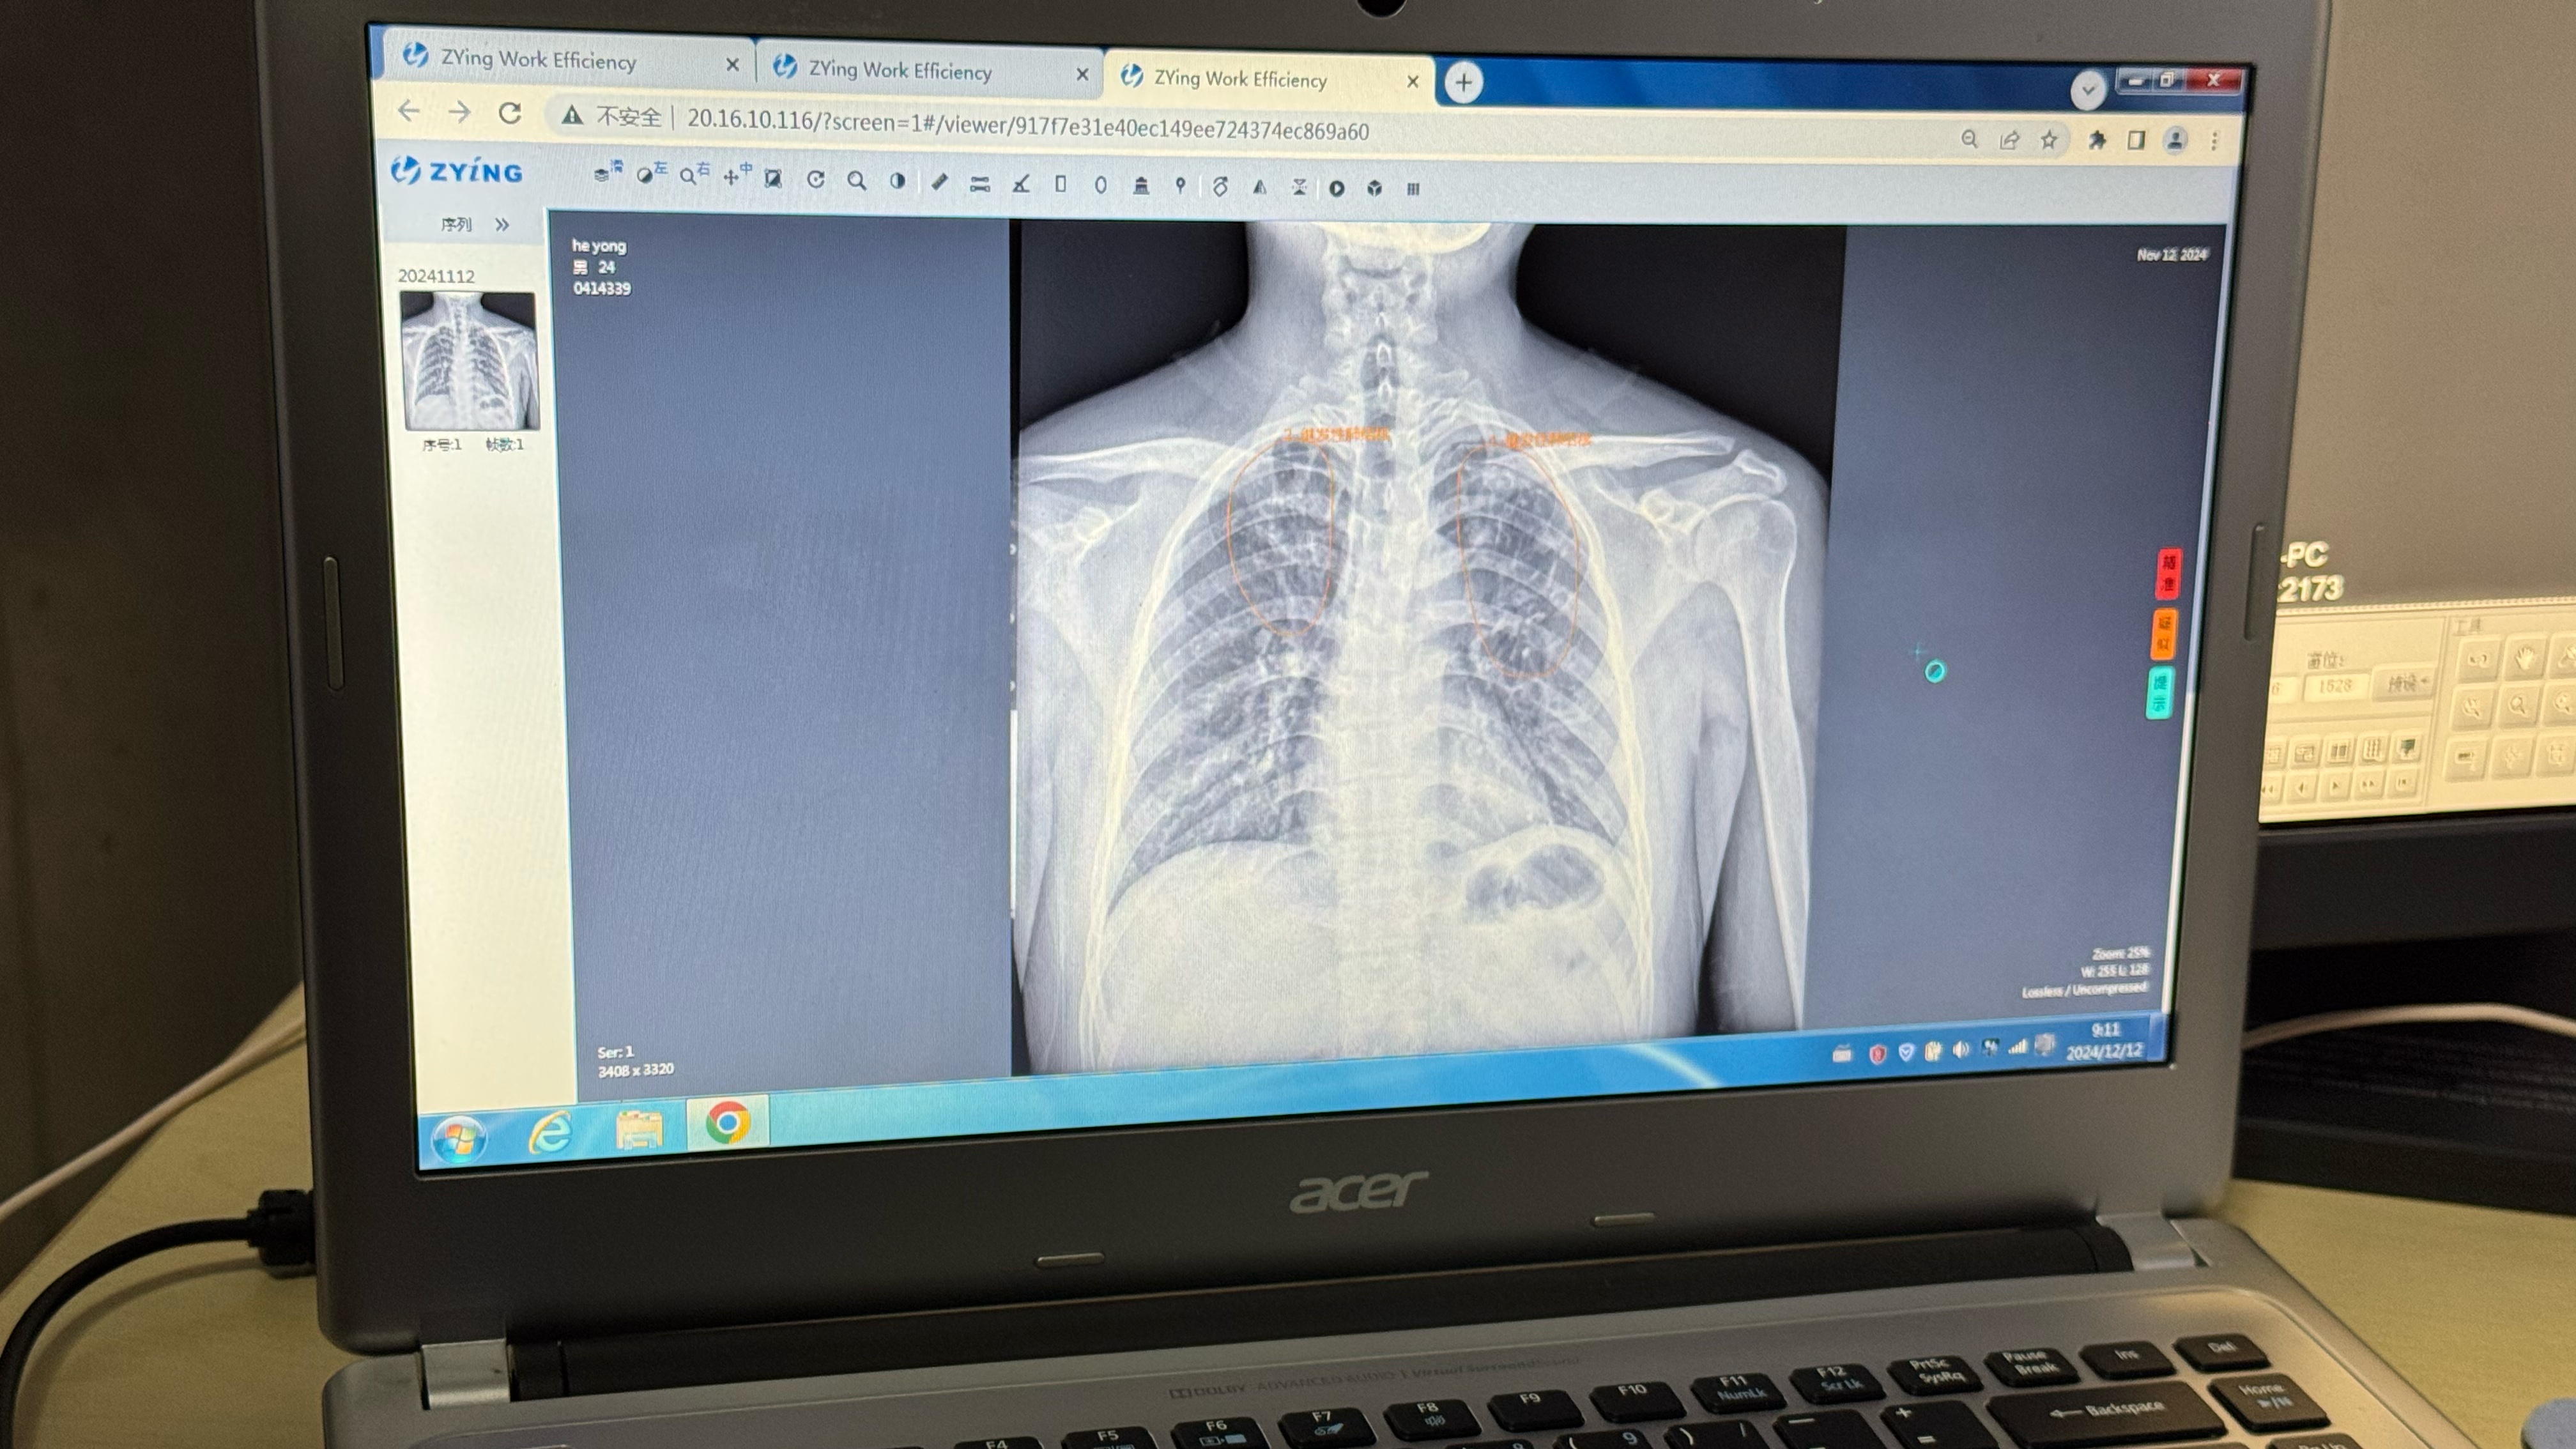

记者在江苏省造访时看到,通过将东说念主工智能阅片模子装入影像科云平台,全省通盘公立病院和部分民营病院的医疗机构杀青互联互通,约略快速筛查患者胸片可疑病灶,并生成自动化敷陈。

“AI赋能有用提高筛查后果和会诊精确度,尤其是不才层医疗机构阐明了遑急作用。”江苏省疾控中心慢性传染病驻守收尾所长处竺丽梅说。

江苏省昆山市第一东说念主民病院锦溪分院辐射科AI云平台阅片系统。新华社记者顾天成 摄

从AI筛查到全程数据照拂,再到全自动一体化袖珍核酸检测系统,科技不仅优化了传统筛查经由,也为“无结核社区”修复、杀青“首诊即确诊”提供了翻新处治决策。

江苏省昆山市第一东说念主民病院锦溪分院辐射科主任汤青燕示意,AI技能不仅能为肺结核筛查提供辅助,还促进了包括肺炎、肺癌在内的多种肺部疾病早期发现和会诊。